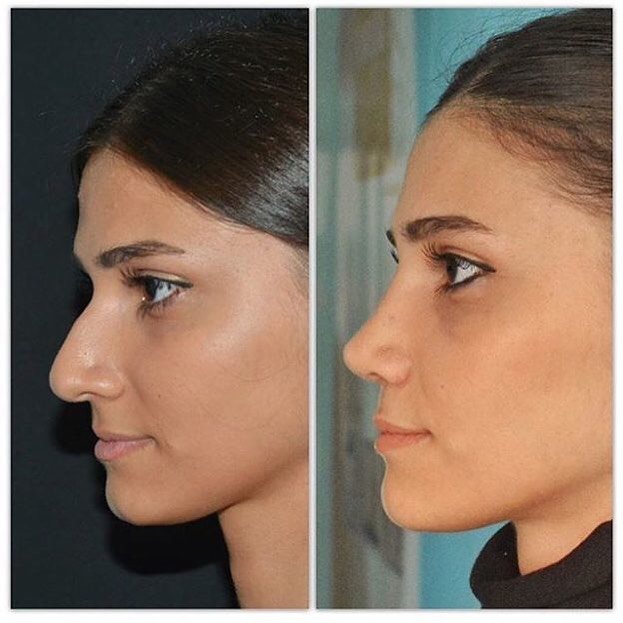

İşlemlerimiz

Önce-Sonra